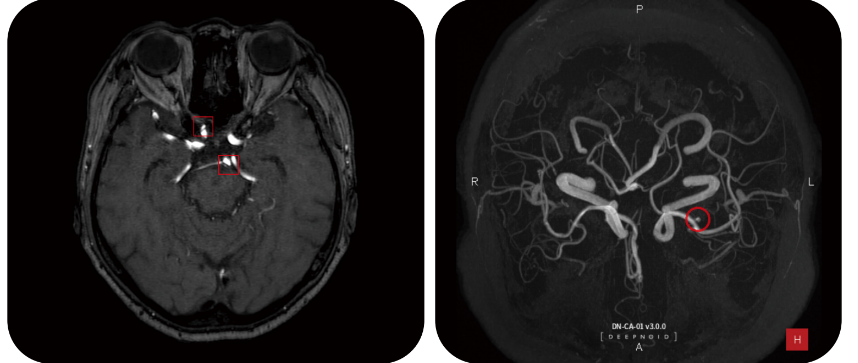

![[사진1] 딥뉴로 판독화면](https://static.wixstatic.com/media/e28c14_2bd4b0fec2674cb98e2d10973e0b434e~mv2.png/v1/fill/w_858,h_363,al_c,q_85,enc_avif,quality_auto/e28c14_2bd4b0fec2674cb98e2d10973e0b434e~mv2.png)

대도시가 아닌 지방에서 부족한 수의 의료진을 도와 높은 정확도로 질단을 보조할 수 있는 솔루션이 필요하다. DEEP:NEURO(딥뉴로)는 이러한 의료현장에서 2nd opinion을 제공함으로써 높은 수준의 뇌동맥류 판독이 이루어질 수 있도록 도움을 줄 수 있다.